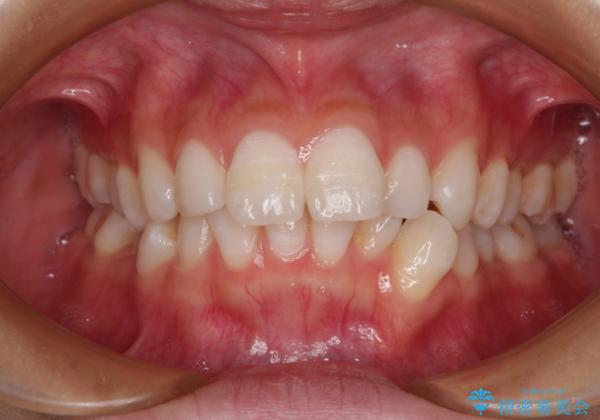

下唇に前歯が当たって跡が残ってしまう状態でしたが、スッキリとした口元に仕上げることができました。